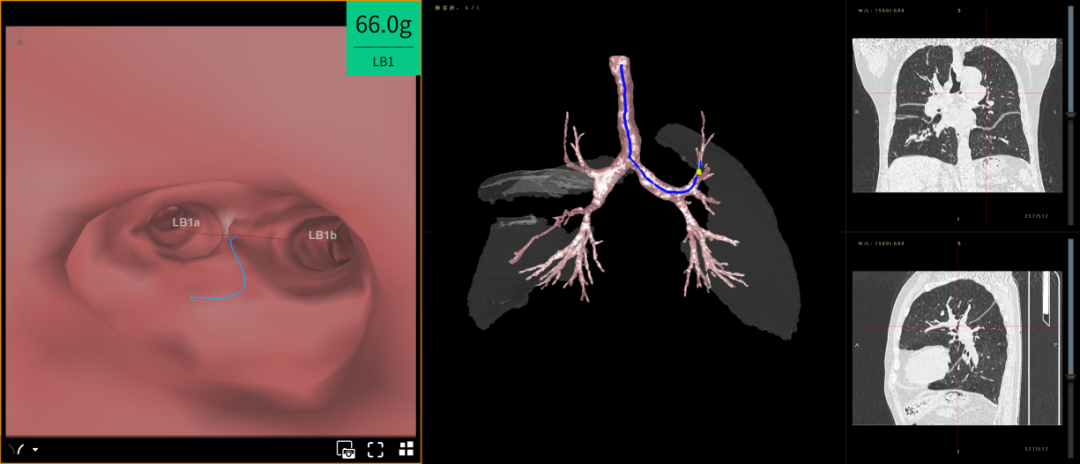

呼吸一病区医疗团队评估后认为邹嗲符合热蒸汽消融肺减容术手术指征,在取得患者及家属同意后,特请胸外科、麻醉科、心内一科、影像科、肺功能室等科室开展多科会诊。会诊同意手术后,7月24日,手术团队在静息复合全麻下为邹嗲行经支气管镜热蒸汽消融肺减容术,手术进展顺利,目前邹嗲已转入普通病房,呼吸情况得到明显改善,正在日益康复中。

利用支气管镜介入技术,通过消除过度膨胀功能低下的病变肺段,为周边更优功能肺段创造空间方式,来提高患者肺功能和生活质量。手术时间15分钟左右即可完成,无植入物,安全性高,减容效果3-6个月逐渐显现,6个月达到最佳,是中重度慢阻肺病人一项新的治疗方案。

是指通过经支气管内窥镜热蒸汽消融治疗术将热的水蒸汽输送到靶肺段进行消融以实现肺减容,减容后为正常的肺组织留出空间,提升病人呼吸的机械效率。适用于GOLD评级3-4级,经充分药物及康复治疗不佳的非均质性(双上肺)肺气肿患者的治疗。